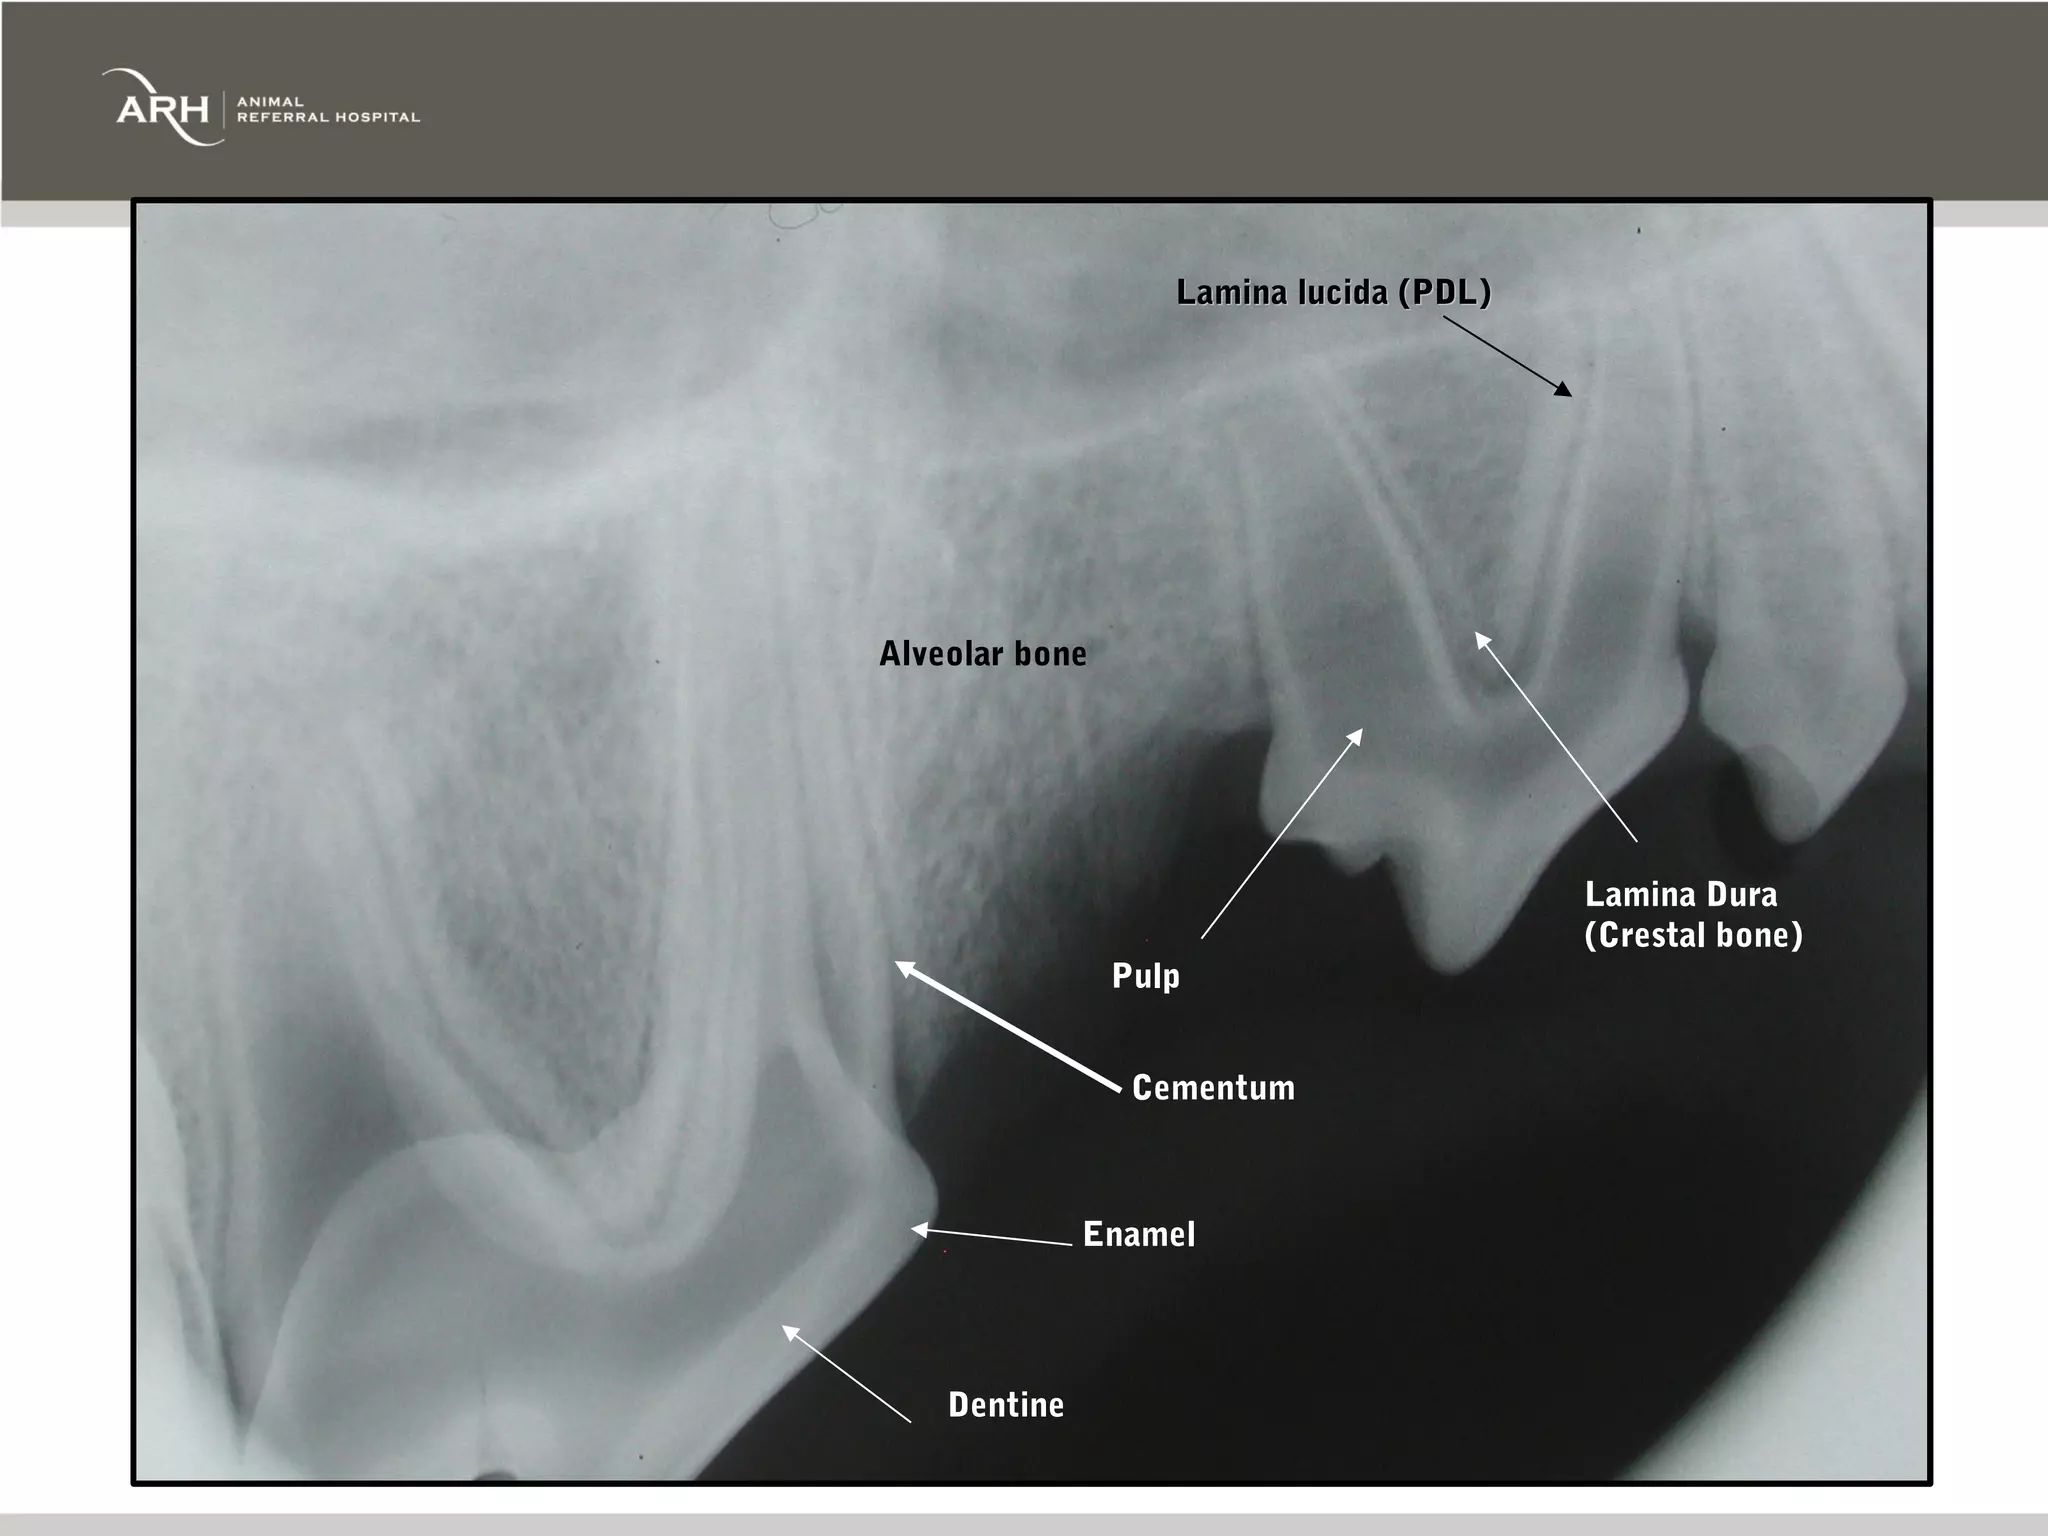

Lamina lucida (PDL) Alveolarbone Lamina Dura (Crestal bone) Pulp Cementum Enamel Dentine